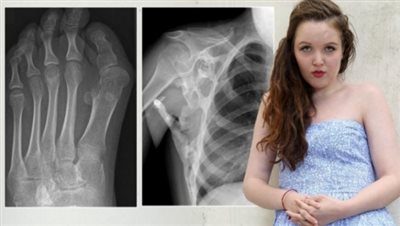

Οι πάσχοντες από τη νόσο, που τελικά αποβαίνει μοιραία για τον ασθενή, βιώνουν την τρομακτική εμπειρία σταδιακά οι μύες, οι τένοντες και οι άλλοι μαλακοί συνδετικοί ιστοί τους να «κοκαλώνουν», μετατρεπόμενοι σε οστά, με αποτέλεσμα ο ασθενής να αποκτά έναν δεύτερο σκελετό που «φυλακίζει» και ακινητοποιεί το σώμα του.

Ένα μωρό που έχει τη νόσο, γεννιέται συνήθως με παραμορφωμένα τα δύο μεγάλα δάχτυλα των ποδιών, ενώ η οστεοποίηση αρχίζει αργότερα από την περιοχή του λαιμού και των ώμων. Αργότερα, δυσκολεύονται να μιλήσουν, να φάνε και να αναπνεύσουν κανονικά. Μόνη θεραπευτική απάντηση μέχρι τώρα είναι η χορήγηση φαρμάκων για τον πόνο.

Η νόσος προκαλείται από μεταλλάξεις, κυρίως στο γονίδιο ACVR1 που ελέγχει την ανάπτυξη των μυών και των οστών και έχουν ως συνέπεια την ανεξέλεγκτη ανάπτυξη των τελευταίων. Συχνά διαγιγνώσκεται λανθασμένα ως καρκίνος, ενώ η απόπειρα χειρουργικής επέμβασης συνήθως κάνει τα πράγματα ακόμη χειρότερα για τον ασθενή.